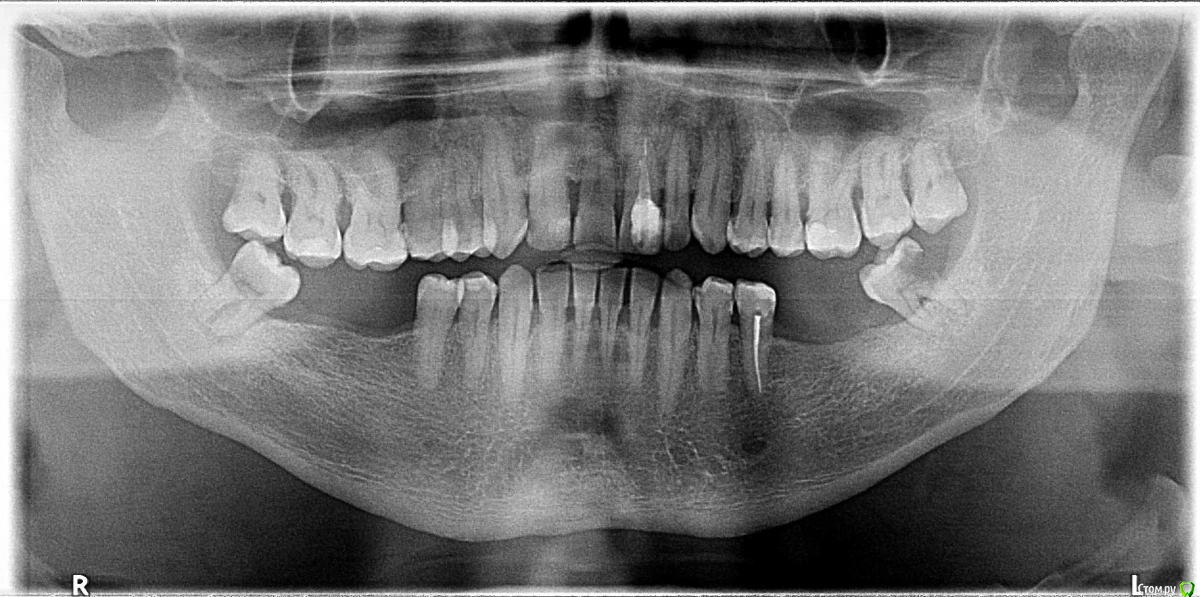

AVS_1970 Опубликовано 10 июля, 2017 Поделиться Опубликовано 10 июля, 2017 Здравствуйте Прошу специалистов высказать мнение с целью помочь сделать мне выборСсылка на Гугл Диске ОПТГОбраз диска с КТ (Daemon Disk Lite) Обошёл 4 клиники в городе: А, Б, В, ГПолучил осмотр и планы лечения.Оплачивал снимки и консультации ( в некоторых и консультации и снимки были бесплатными)Во многом планы похожи, но есть индивидуальные отличия, некоторые из которых встречаются только в одной клиники.Квалификация врачей примерно одного уровня (высокая, судя по отзывам) В клиниках Б и Г имплант устанавливает и делает коронки один человекВ клиниках А и В имплантолог и ортопед разные врачи.Предложения врачей по лечению (количество клиник предложивших вариант и буквенный код)Зубы 38, 48 удалить - 4/4Зубы 28 и 18удалить сразу - 2/4 (А и Б)не трогать пока не беспокоят 1/4 (Г)удалить в течении года-двух не дожидаясь ухудшения 1/4 (В)Зубы 36, 37, 46, 47 - имплантацияс пластикой мягких тканей - 1/4 (А)с пластикой мягких тканей и наращиванием кости слева 1/4 (Б)без дополнительных манипуляций - 2/4 (В и Г)21 зубпопробовать спасти 1/4 (В)имплантация 4/4 (если не сработает вариант спасти)одномоментная 3/4 (А, Б, Г)удаление зуба, лечение кисты и через месяц имплантация - 1/4 (В)с пластикой мягких тканей - 1/4 (А)с пластикой мягких тканей и формированием круглой лунки при необходимости - 1/4 (Б)с пластикой мягких тканей в случае необходимости после приживления - 2/4 (В и Г)Коронки решил ставить безметалловыепо системам клиники предлагаютА- Osstem, NobelБ - Dentium, Impro, StraumannВ - Astra, Dentium/SuperlineГ - AnyOne, Impro, StraumannМне близка и понятна схема:а) 38 и 48 -удалятьб) 18 и 28 не трогать пока не станут беспокоитьв) 21 удалятьг) лечить кистуд) ставить импланте) пластику мягких тканей делать при необходимости В чем я не прав?Стоит ли доверять врачу который планирует уникальные манипуляции (типа наращивания кости или обязательной пластики мягких тканей)?Врач имплантолог и ортопед в одном лице это явный плюс или я ошибаюсь? Так же прошу высказаться по нижеследующим вопросам:Из систем выбрал в порядке убывания приоритета1.Astra и Straumann (дорого, опыт наблюдений и статистика, гарантия того, что запчасти не исчезнут с рынка мгновенно и навсегда (кроме катаклизма), на пределе фин. возможностей с учетом стоимости коронок)2. Dentium/Superline и Impro как я понял это копии с Астры, значит у Астры хорошая система раз копируют. Более щадящий в финансовом плане вариант.3.Есть ли смысл экономить ставя на передний зуб систему из пункта 2?4.Стоит ли обращать внимание на гарнтию на имплант (кусок титана сломать можно, я понимаю) или искать гарантию в виде бесплатной замены импланта в случае отторжения в сроки более года.5.Или просто чистить зубы и раз в год проходить проф чистку в клинике?6.Ваше мнение по срокам службы системы имлант+коронка в нормальных условиях Прошу прощения за большое количество вопросов. Ссылка на комментарий

AVS_1970 Опубликовано 11 июля, 2017 Автор Поделиться Опубликовано 11 июля, 2017 (изменено) Спасибо за отклики 21й зуб спасать. За что решили удалять 21? у него достаточно высокие шансы на перелечивание. Причина: фронтальный перелом, за десной, некачественное предыдущее лечение.Вот что мне врач сказал.Вероятно удалить и сделать имплант для некоторых проще.В конце недели будут смотреть в единственной клинике где предложили "разобрать зуб" и по результатам осмотра вынести вердикт.Даже план лечения выдали . Очень надеюсь на сохранение. пластику десны делать.сразу или после приживления импланта?8-ки удалять все 4 и сразу? Изменено 11 июля, 2017 пользователем AVS_1970 Ссылка на комментарий

AVS_1970 Опубликовано 13 июля, 2017 Автор Поделиться Опубликовано 13 июля, 2017 Был сегодня на консультации в клинике по 21 зубу - даже не стали "разбирать".Сказали, что перелом глубоко и спасать зуб не возможно. Ссылка на комментарий

Bier Опубликовано 13 июля, 2017 Поделиться Опубликовано 13 июля, 2017 Перелом мы на снимке не видим. Если это так, то врачи правы. 1 Ссылка на комментарий